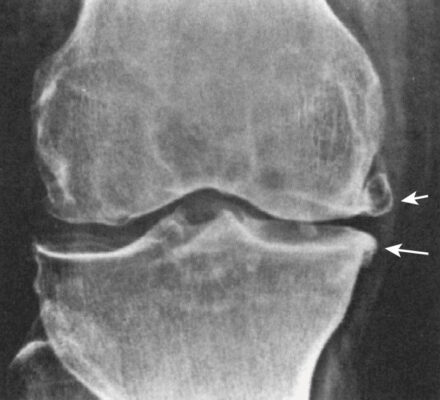

X quang:

- Những thay đổi trên phim X quang bao gồm hẹp khe khớp, đặc xương dưới sụn và các nang xương ở các vùng chịu trọng lượng của khớp và gai xương ở các vùng ít áp lực, đặc biệt là dọc theo các vùng rìa của khớp. Hẹp khe khớp là dấu hiệu đầu tiên, tiếp theo là đặc xương dưới sụn, sau đó là gai xương và cuối cùng là các nang có rìa đặc xương (gọi là các nang hoạt dịch, nang dưới sụn, giả nang dưới khớp hoặc giả nang hoại tử).

- Các dấu hiệu X quang thoái hoá khớp không tương quan chặt chẽ với các triệu chứng; tuy nhiên, sự hiện diện của gai xương và đặc xương dưới sụn có mối liên hệ chặt chẽ với đau đầu gối, trong khi hẹp khe khớp không liên quan đến đau. Mức độ đau đầu gối là yếu tố quyết định suy giảm chức năng quan trọng hơn so với mức độ nghiêm trọng trên phim chụp X quang.

- Các chỉ định chụp phim X quang thường quy bao gồm chấn thương, tràn dịch, các triệu chứng không thể giải thích được bằng kết quả khám lâm sàng, đau nhiều, để lập kế hoạch trước phẫu thuật và thất bại trong điều trị bảo tồn .